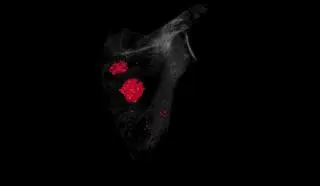

Badanie tomografii komputerowej czaszki

Po analizie uszkodzeń kości biegli chcą ustalić, jak zginęli żołnierze na Westerplatte

W trakcie prac biegli zbadali wszystkie znalezione kości. Stwierdzone zmiany dokładnie opisali i sfotografowali. Biegły radiolog zlecił i wykonał badania tomografii komputerowej wybranych elementów szkieletów, żeby zweryfikować uszkodzenia.

Instytut Pamięci Narodowej w Gdańsku przesłał do mediów również film, na którym zilustrowano wyłamanie około połowy kości pokrywających część mózgową czaszki i większość kości części twarzowej czaszki. Strzałkami i czerwonym kolorem na kolejnych zdjęciach zaznaczone są odłamki metalu wbite w kości czaszki.